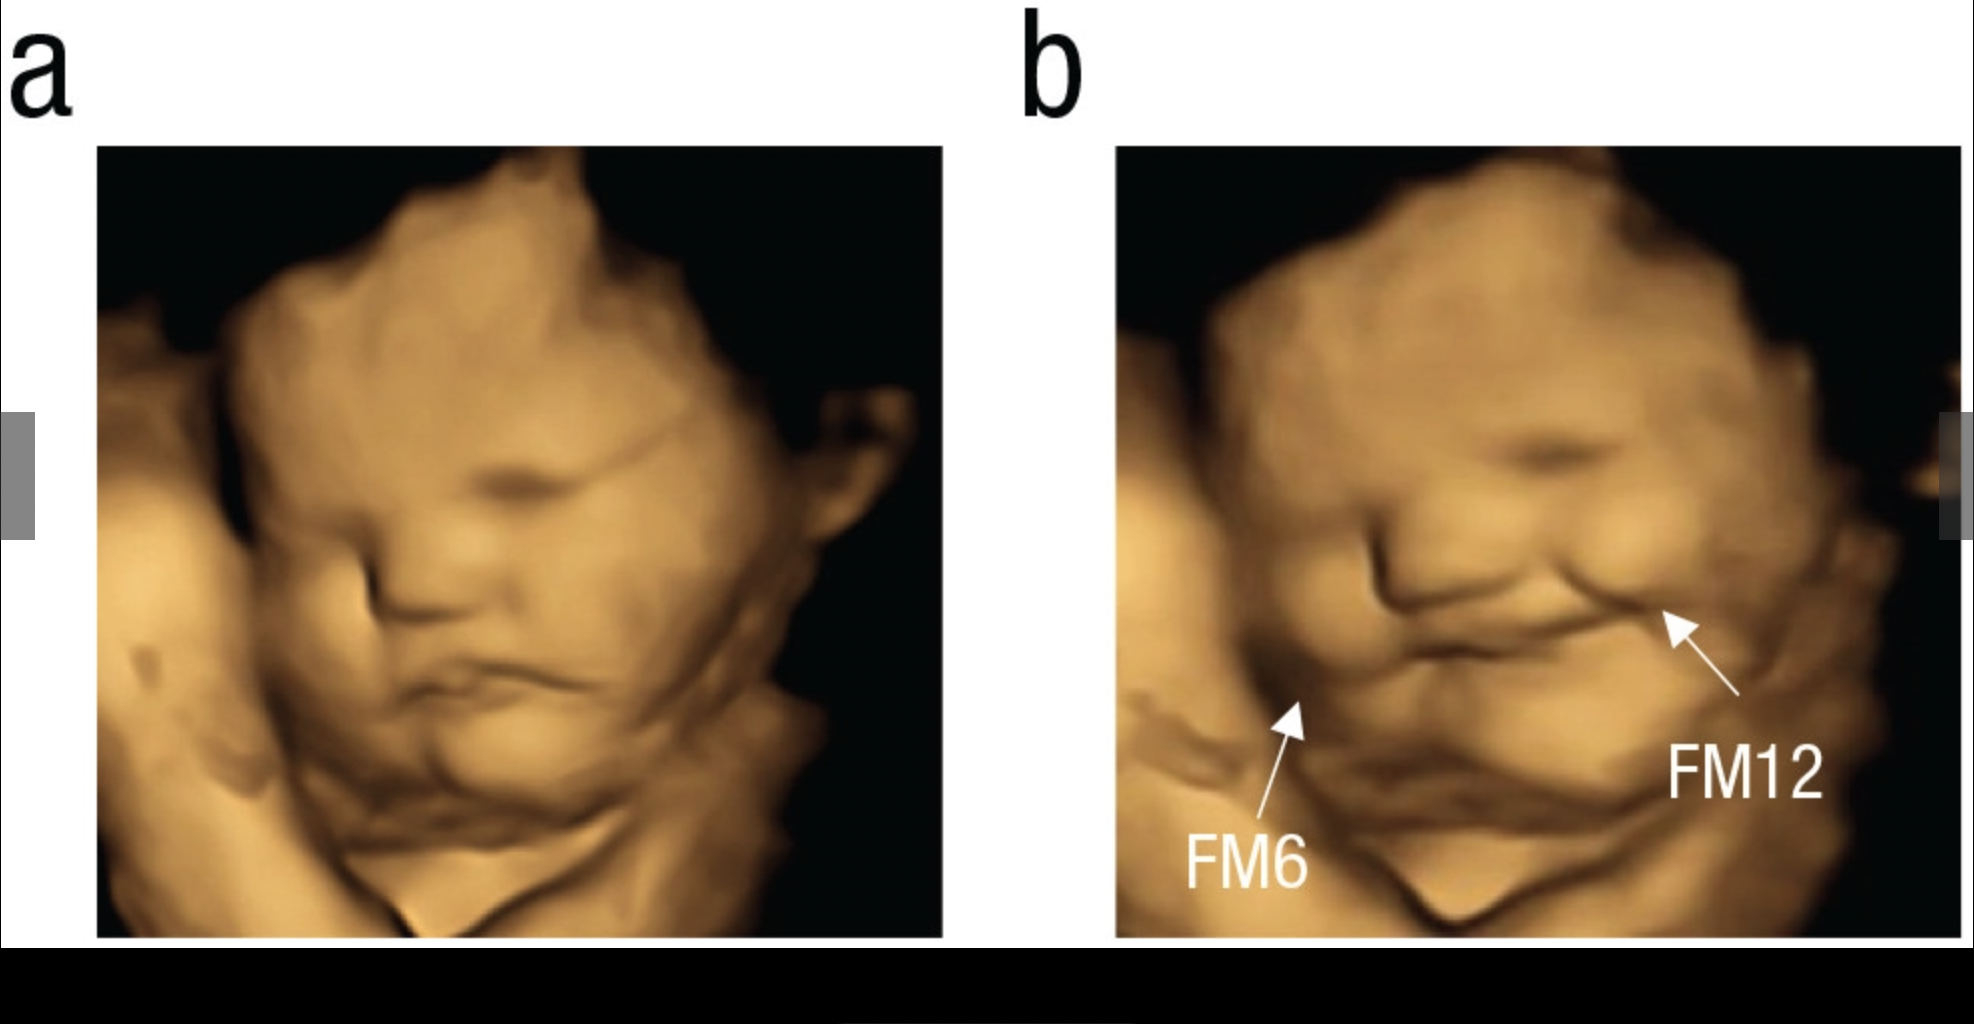

One hundred pregnant women from the U.K. were given powder with either carrot or kale flavoring or neither flavor. After 20 minutes, 4D ultrasound scans revealed undeniably different—and kind of hilarious—facial reactions. It was very telling which flavor was smile inducing and which one wasn’t.

As the picture below shows, the carrot flavor induced a smiling “laugh face,” as the study called it.

This look of pleasure could be as a result of a preference for sweetness, which newborns are known to gravitate to as a basic biological drive.